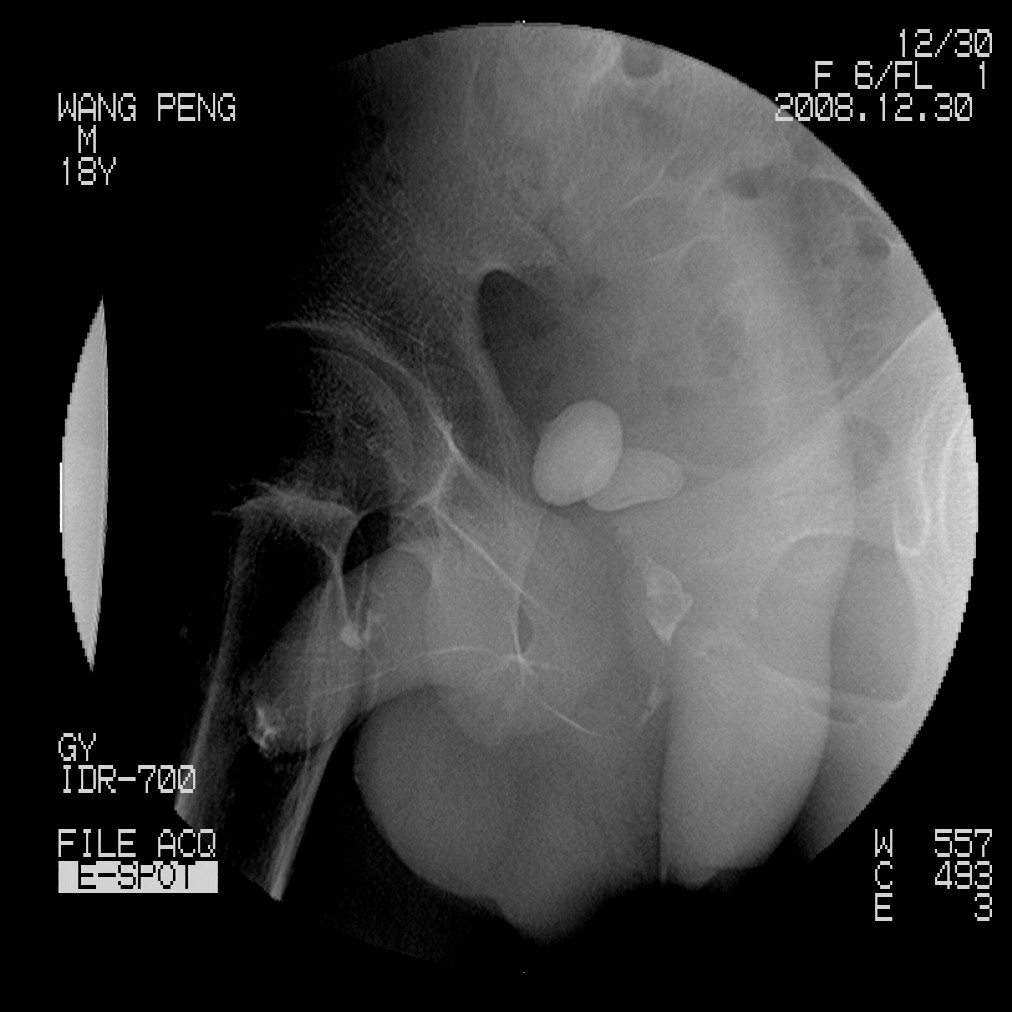

标题: X6910:经典的膀胱及尿道多发结石 [打印本页]

标题: X6910:经典的膀胱及尿道多发结石

患者,男,18岁,尿流不畅数月。

膀胱及后尿道多发结石,谢楼主分享

膀胱及尿道多发结石。

膀胱及后尿道多发结石,谢谢分享---------------------------